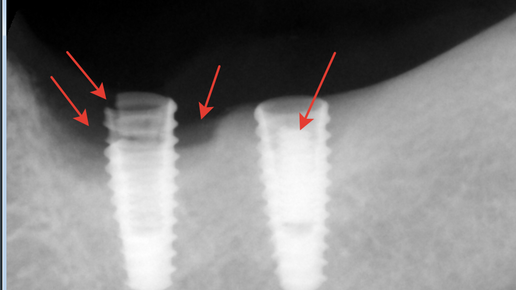

📌Принципы фиксации коронки на имплант Способ установки протеза зависит от метода имплантации: 🗒Виды крепления Существует три основных метода крепления коронок: Чаще применяется два основных вида установки: винтовой и цементный. ✳Зубная коронка с винтовой фиксацией 🔹Положительные моменты винтового способа крепления: 🔹Недостатки: ✳Чем отличается от крепления на цемент 🔹Отличия цементного способа от винтового: 🥴Осложнения, связанные с винтовыми соединениями Между абатментом и имплантатом есть наиболее уязвимое место, при этом на него приходятся основные нагрузки...